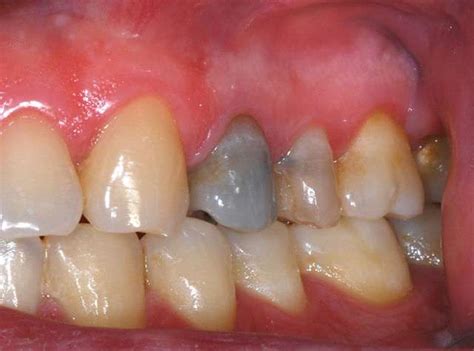

- Endodoncia previa: Se produce cuando se ha realizado una endodoncia en el diente o dientes. El diente oscuro por tratamiento de conducto puede ocurrir por varios motivos. Por ejemplo, debido a una necrosis pulpar o presencia de sangre. Hay materiales, por otro lado, que se utilizan durante las reconstrucciones que pueden provocar la aparición de manchas.

En primer lugar, hay que determinar si la coloración se debe a una caries y si la raíz está comprometida. Si es así, significa que no es posible salvar el diente. Cuando el origen es una caries y esta no ha afectado la raíz, se puede hacer una endodoncia para eliminar infección. Después de limpiar y sellar se pasa a la restauración estética, que puede hacerse mediante una carilla o corona.

Los traumatismos en los que no se haya producido fractura radicular también se pueden solucionar con una endodoncia, que se completa con una rehabilitación dental. Luego se hace un blanqueamiento interno para devolver la tonalidad blanca. En cambio, si el golpe dañó la raíz, entonces la solución es extraer la pieza y reemplazarla con una prótesis dental.

- Para dientes que han oscurecido después de un traumatismo o una endodoncia no bien realizada, es común realizar un blanqueamiento dental interno.